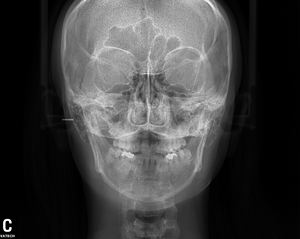

パノラマは大体どこの歯科医院にもあります。「セファロ」は顎顔面の状態をきちんと把握し、正しく治療を行う上で必要な横顔と正面から撮影したレントゲンです。

このセファロの撮影方法としては主に

デジタル方式の中でも最も少ない被ばく量の、ワンショットセファロを導入しました。今まで「最新」と言われていたデジタル方式では、アナログと比較して被ばく量が少ないものの、機種によって3秒から15秒近くの撮影時間が必要でした。その間、じっとしていないといけないわけですが、お子さんの場合は「じっとしていてね」といってもよけいに緊張して動いてしまう場合があり撮り直しすることがありました。

ワンショットタイプですと、撮影時間が0.5秒であっというまに終わります。

放射線を浴びる時間が0.5秒に短縮されます。

また、少し詳しい話になりますが、撮影した画像を感知するCCDというセンサーが従来品では顔の大きさより小さいため、縮小撮影してから大きく引き伸ばすため、画像が荒くなり細かい骨の状態が確認しづらいことがありました。当院で導入した京セラ製ワンショットセファロは、画像をそのままの大きさで撮影しますので、より

クリアーな画像で誤診を防ぎます。